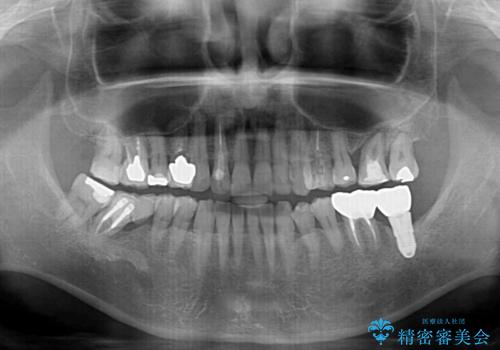

- 60歳を越え、黄ばんだ前歯をセラミッククラウンできれいな口元にしたいとのことで来院された患者様です。

診察したところ、前歯は反対咬合であり、その影響で抜歯が必要な奥歯があることが分かりました。

抜歯が必要な奥歯は、インプラント並びにブリッジにより補綴を行い、上下前歯は反対咬合を改善させるように補綴治療を行うこととしました。

健全な歯を削ってセラミッククラウンに置き換えることは、本来避けるべき治療と考えますが、今回は①患者様が60歳を越えていること、②要改善の咬合により抜歯が必要な奥歯があること、③反対咬合の前歯改善の手段としてセラミック治療が選択肢にあることなどから、全顎的なセラミック治療を行うこととしました。